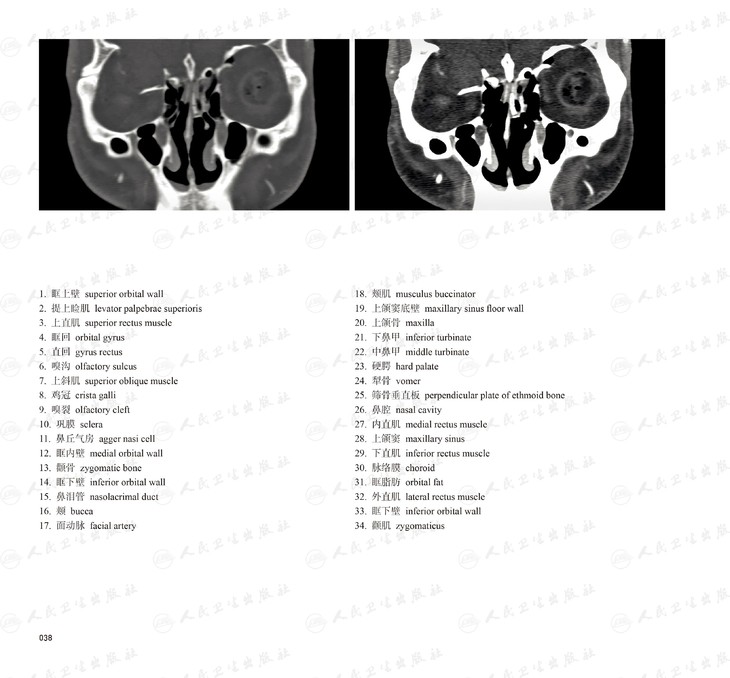

本书从数据集每隔1.2mm选取一幅图像,截取眼、耳、鼻及毗邻颅底的局部区域图像,共112幅图像。同时配以相应部位的CT图像对照。本书特色是断层解剖图利用数字图像处理技术优势,放大并清晰展示眼、耳、鼻及毗邻颅底断面的局部区域结构,组织色泽真实,甚至能够清晰显示肌肉纹理、筋膜纹路等细节结构,图像质量高于美国同类断层解剖彩色图的图像质量。对眼科、耳鼻咽喉科和神经内外科医生理解相关解剖结构有较大帮助。